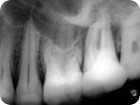

Retratamento Endodôntico

Retratamento Endodôntico 1